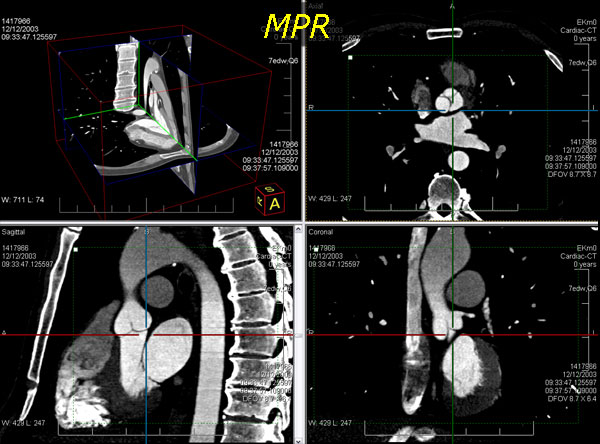

leadtools medical 3d sdk技术简化了二维医学影像切片三维医学可视化的重构技术,如mri和ct栈。leadtools medical 3d sdk技术提供了原始数据的许多不同的替代视图。它使用了三维重构技术如mpr、vrt、mip、minip和ssd,且支持裁剪平面、板、缩放、变焦、相机控制、阈值、透明度和影像处理的投影技术。

通过提供可视化的解剖细节,体数据的检查提高了解释、识别的速度和医师总测试评估的时间,这些仅仅利用二维切片是很难诊断的。

使用leadtools medical 3d sdk技术,开发者可创建使用任意二维横截面切片堆生成三维模型的应用程序。为了生成有意义的三维模型,横截面必须互相平行,因此leadtools提供了使用dicom标签识别、分离和设置体积栈的功能。

同时,leadtools medical 3d sdk提供了一个接口,可定义三维像素(体素)模型,还可通过三维模型的正确测量、方位标注和缩放进行患者定向,并生成斜交切片和正交切片。

向leadtools medical 3d sdk engine添加横截面切片后,开发者通过简单地设置所需的模型类型属性即可在不同的模型类型间转换。leadtools medical 3d sdk engine支持以下的三维模型类型(点击模型类别查看截图):

leadtools medical 3d控件也能生成斜交和正交的二维mpr切片。通常情况下,一个mpr视图包括显示所需结构的三个正交平面视图和操纵这个体的方法。leadtools?medical 3d控件允许每个生成的二维正交平面(轴向、矢状和冠状)和独立的leadtools medical viewer 控件单元联系在一起。在这个配置中,leadtools?medical image viewer和leadtools medical 3d控件共同提供了交互式的三维光标同步和任意正交平面的支持。

leadtools medical 3d sdk提供了二维正交mpr平面的交互式板控制。当三维体板功能启用时,leadtools medical image viewer控件使用每个二维mpr平面上的虚线矩形显示板的边界。用户可以使用鼠标拖拽曲线调整裁剪平面。